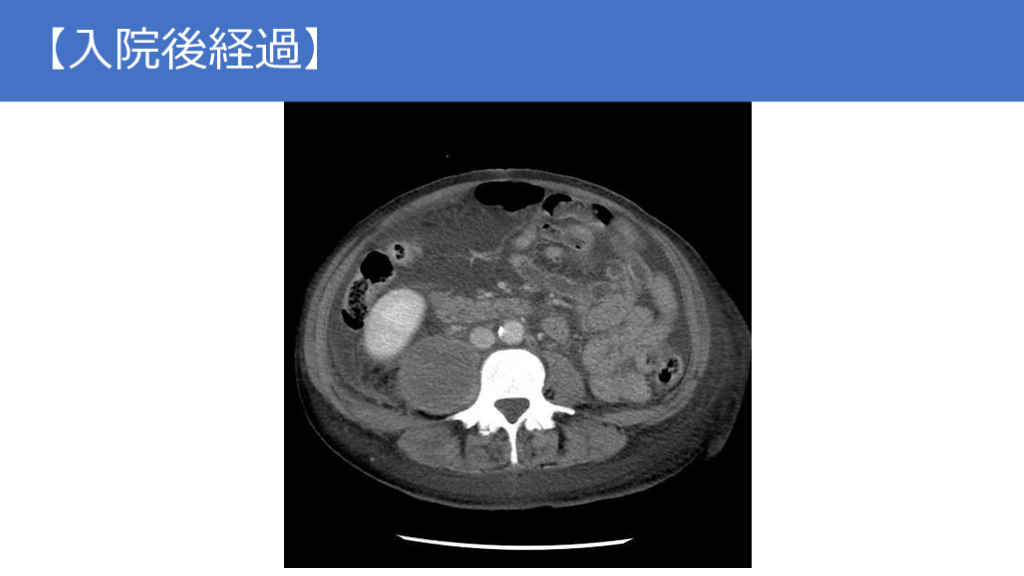

【頭部・胸腹部単純CT】 9/1

【画像所見まとめ】 新規に胸腹水貯留(20HU) 門脈周囲にびまん性に低吸収あり 硬膜下血腫は縮小傾向 軟部組織に脂肪識濃度上昇あり 左鎖骨上に造影効果のある1cm程度のリンパ節